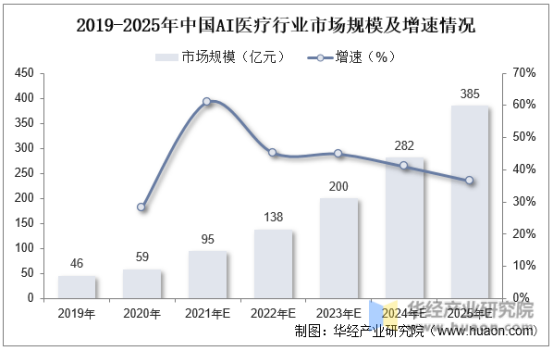

目前来看,虽然由于产业生态、技术基础、计算资源等原因,国内AI医疗与国外相比仍有差距,但从市场增速和规模上看,国内在AI医疗的发展上有较大的市场空间和增长潜力,面临着较高的医疗需求。

根据华经产业研究院的数据,2021年中国AI医疗行业市场规模约为95亿元,预计2025年达到385亿元。

资料来源:华经产业研究院